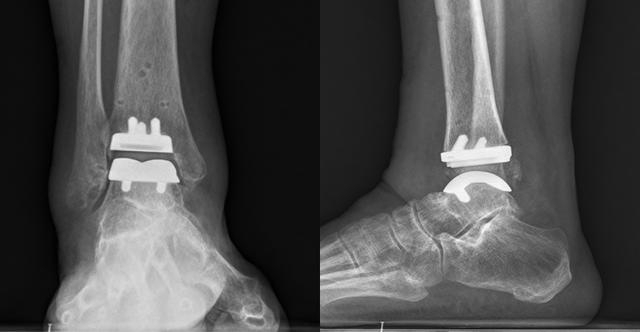

術後複查右踝關節片。通訊員 供圖